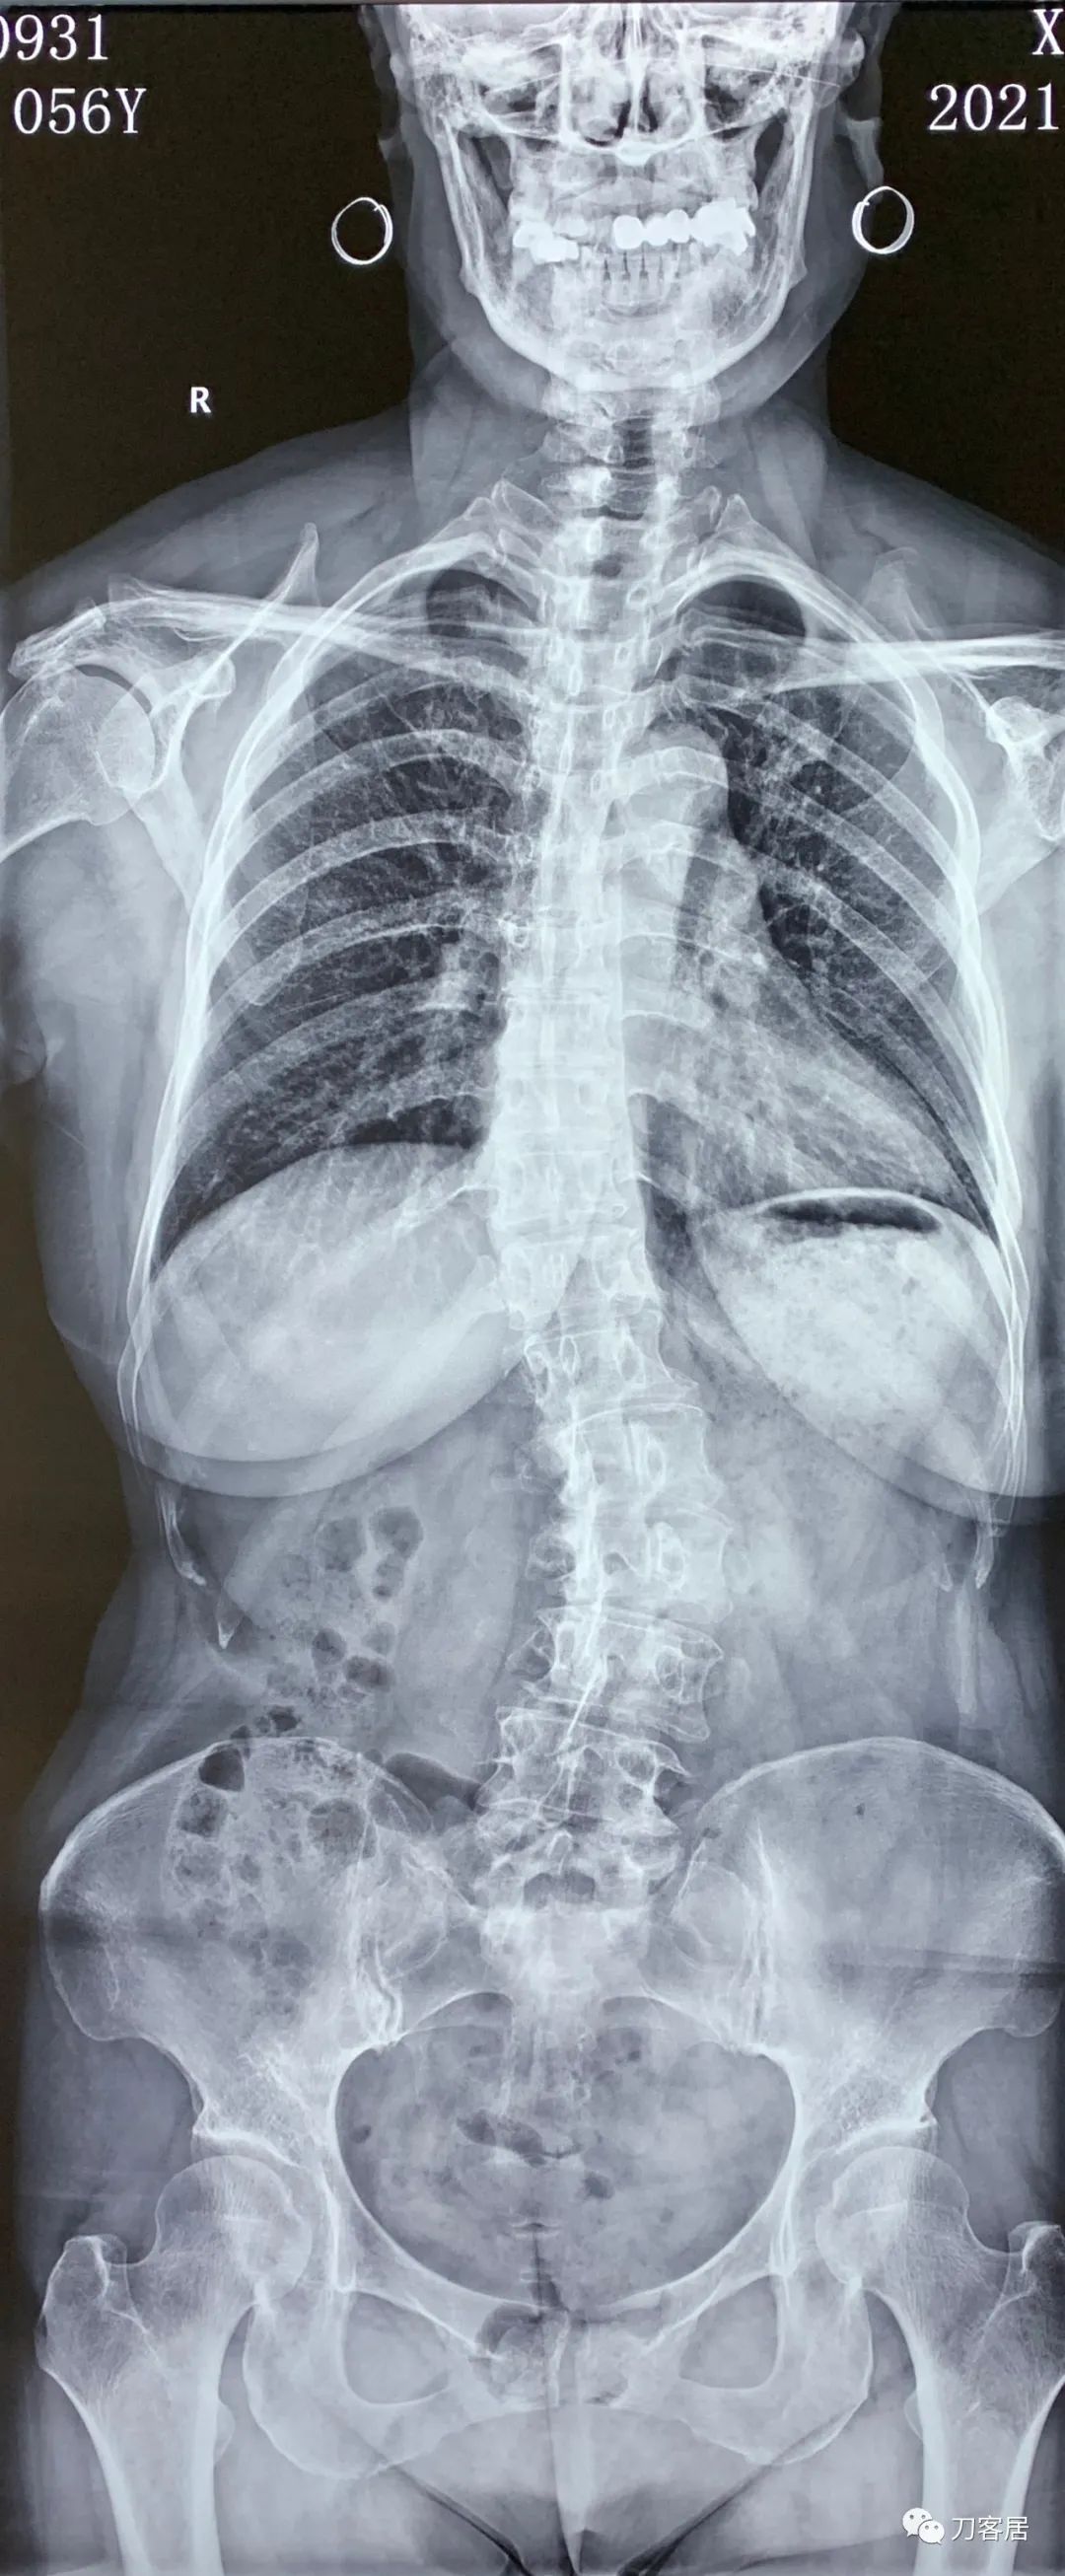

2021年12月12日去渭源县医院做颈椎腰椎MRI,提示1.腰椎侧弯畸形并骨质增生,2. L5S1椎体终板炎(I型), 3. L1-S1椎间盘变性并腰2-4,腰5骶1椎间盘膨出,腰4-5椎间盘突出并相应平面继发性椎管狭窄。2020年12月中旬于渭源县医院行骶管注射2次6针后睡眠改善,

2021年5月17日,西京医院骨科门诊找我就诊,自带影像学检查资料提示腰椎侧弯,腰3-4,腰4-5椎间盘突出,黄韧带肥厚,椎管狭窄。

建议其查双光子骨密度,骨盆正位片以及腰椎间盘平扫。腰椎正侧位X线片以及动力位片,站立位脊柱全长正侧位X线片,以了解其是否有骨质疏松,并了解脊柱侧弯情况,腰椎局部X线表现情况和腰椎间盘突出和椎管狭窄情况。

从这个患者的影像资料分析,颈椎间盘突出问题不大,没有明确的上位神经元损伤表现,所以,不考虑颈椎和胸椎问题。腰椎侧弯畸形,但不严重。因为存在腰椎侧弯,使得腰椎MRI在扫描切面的时候,显示的椎间盘突出或椎管狭窄会有一定的误差,所以,又加做了经椎间盘的CT平扫,影像表现并不严重,综上,腰椎间盘突出,腰椎管狭窄,腰椎侧弯,不考虑手术治疗。同时,患者的主要痛苦是心理疾病,而不是器质性疾病,所以,以心身疾病治疗为主。虽然患者骨密度检查结果提示正常,但X线片显示骨质疏松,且其症状也与骨质疏松的症状有符合之处,比如静息痛,不能入睡,动作及姿势变换时痛加重等,所以,给予实验性抗骨质疏松治疗,以观疗效。